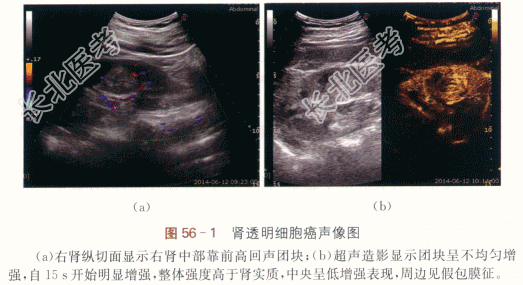

右肾透明细胞癌。